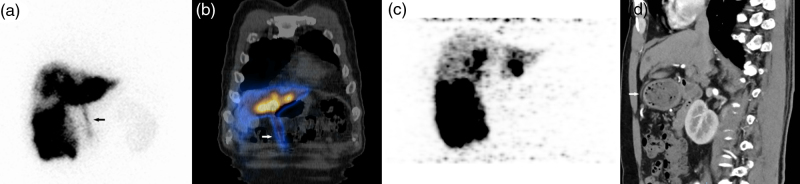

目的:探讨90Y树脂微球选择性内放射治疗(SIRT)中前腹壁(AAW)放射性示踪剂积累的差异模式,采用99mTc-MAA单光子发射计算机断层扫描(SPECT/CT)和90Y正电子发射断层扫描(PET/CT)对前腹壁(AAW)放射性示踪剂积累的影响。材料与方法:回顾性分析2022年8月至2024年11月期间接受SIRT治疗的204例不可切除肝脏恶性肿瘤患者。治疗前评估包括诊断性血管造影和99mTc-MAA成像。治疗后24小时内进行90Y-PET/CT检查微球分布。分析99mTc-MAA图像或90y微球PET/CT图像上AAW积累的患者,并以至少3个月的随访结果作为参考标准。结果:204例患者中,21例(10.3%)在99mTc-MAA图像或90y微球PET/CT图像上显示AAW积累。99mTc-MAA影像与90Y-PET/CT影像一致的有11例(11/21,52.4%),仅在90Y-PET/CT影像上有堆积的有5例(5/21,23.8%),仅在99mTc-MAA影像上有堆积的有5例(5/21,23.8%)。2例患者发现肝镰状动脉(HFA)。4例患者出现轻度腹痛,仅有1例患者出现腹部皮炎,并自行消退。其余患者在随访期间未出现任何相关副作用。结论:aaw相关的并发症罕见且轻微,提示HFA专利可能不被认为是SIRT的禁忌症;然而,99mTc-MAA和90Y-PET/CT之间的不一致强调了治疗后警惕监测的必要性,即使在治疗前没有AAW积累的病例中也是如此。

Results: Among 204 patients, 21 (10.3%) showed AAW accumulation on 99m Tc-MAA images or 90 Y-microspheres PET/CT images. Concordant findings between 99m Tc-MAA images and 90 Y-PET/CT images were observed in 11(11/21, 52.4%) cases, while five cases (5/21, 23.8%) showed accumulation only on 90 Y-PET/CT images, and the other five cases (5/21, 23.8%) showed accumulation only on 99m Tc-MAA images. The hepatic falciform artery (HFA) was found in two patients. Mild abdominal pain was observed in four patients, and only one patient experienced abdominal dermatitis, which resolved spontaneously. The remaining patients did not experience any relevant side effects during the follow-up period.